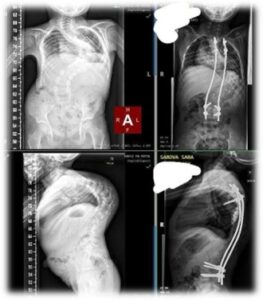

Vo veku 8 rokov má v chrbátiku kovovú oporu, ktorá jej chrbticu narovnáva. Jej skolióza mala pôvodne zakrivenie až 122°, dnes sa vďaka lekárom, rehabilitáciám a Vašej pomoci podarilo znížiť na 65°.

Posielam Vám aj snímky, kde to pekne vidieť. Je to obrovský krok vpred, no naša cesta ešte zďaleka nekončí. Moje milované dievčatko čaká ďalšia operácia chrbátika a potom operačné zákroky oboch nožičiek.